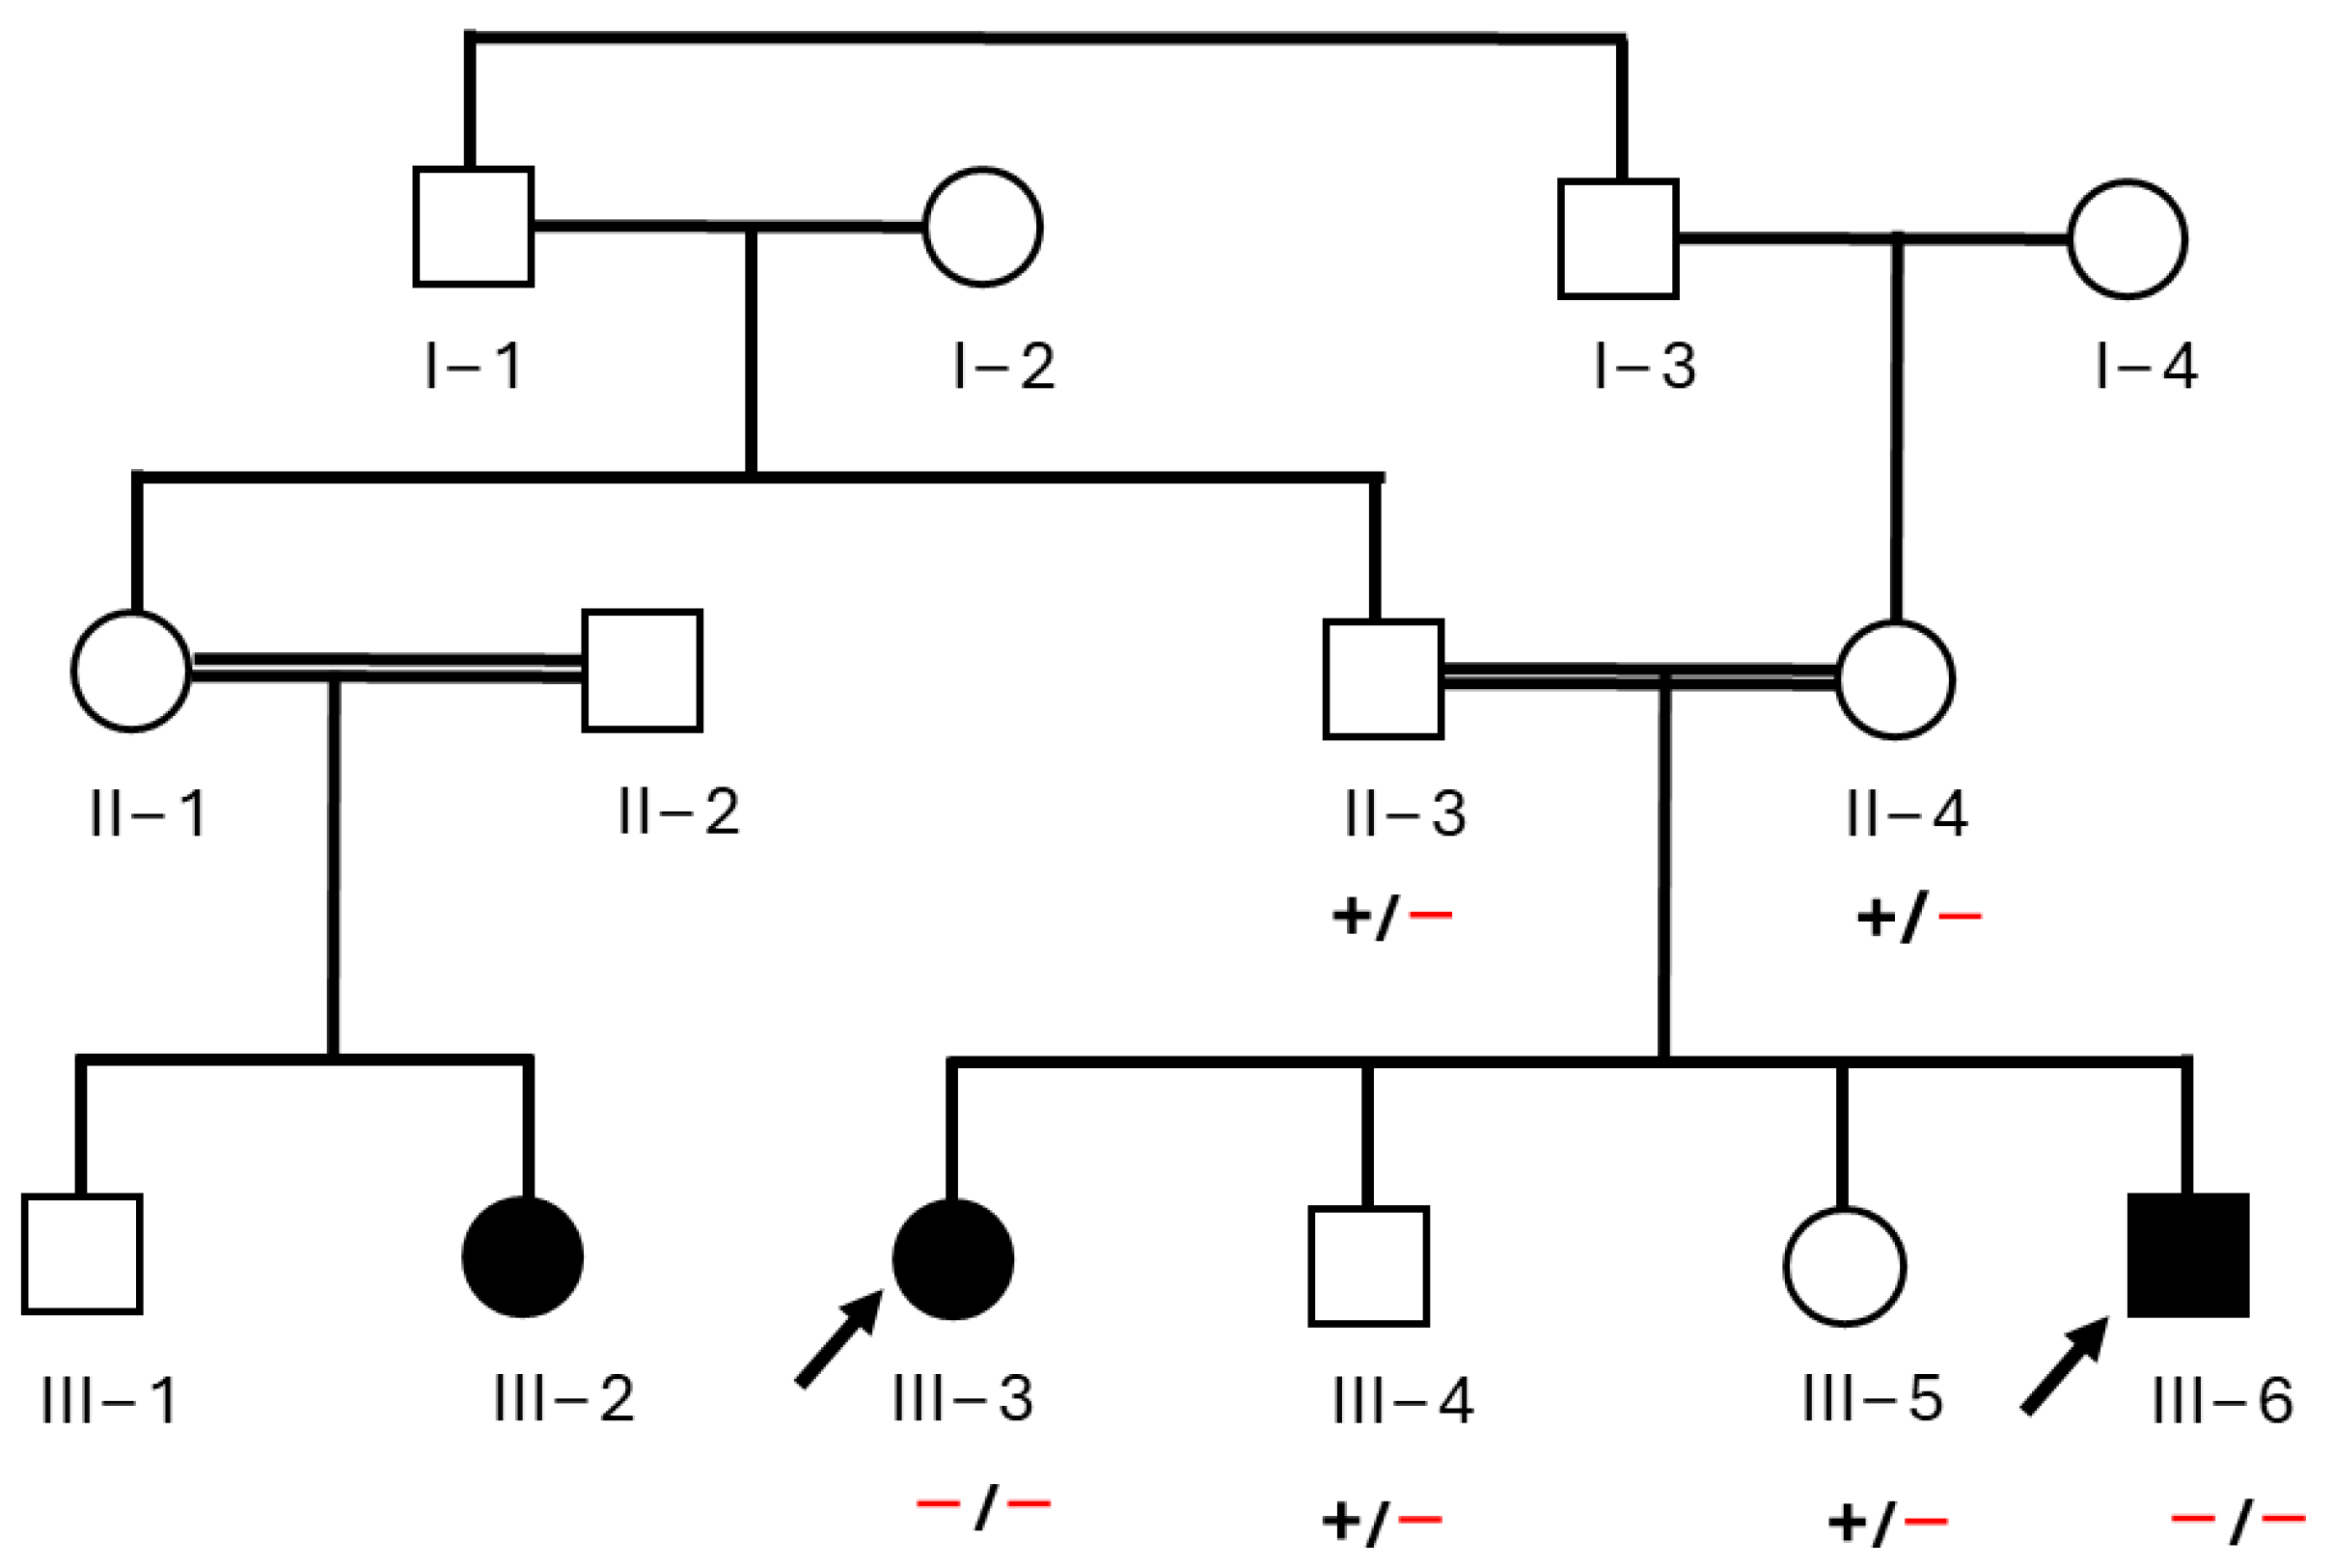

3.1. Clinical Features of Affected Individuals

3.3. Exome Data Analysis and Genetic Assessment